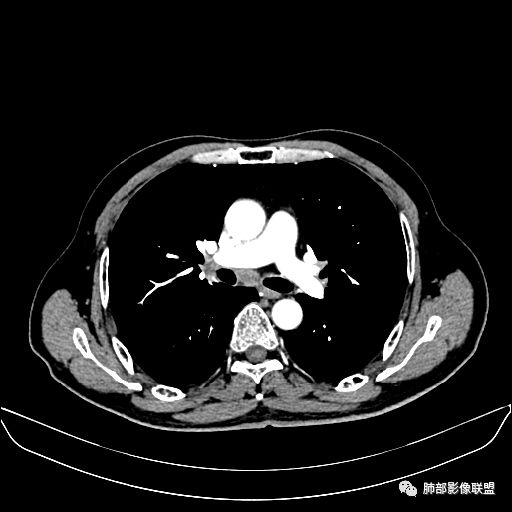

入院CT

老年男性,因“咳嗽咳痰1月余。”入院。病程中咳嗽咳痰,咳黄白痰,间断咯少许鲜红色痰血。PPD阳性。胸CT:右肺中叶外侧段支气管管腔阻塞,大片实性病变,病灶边缘光滑,部分边缘膨隆,可见分叶,肺门及纵隔可见肿大淋巴结,并可见钙化。增强可见病灶明显强化,而且延迟强化明显,病灶内多发低密度区,内见血管影,血管变细、部分血管破坏。考虑恶性病变可能性大,鉴别慢性肉芽肿性病变。

右肺中叶外侧段管腔阻塞、实性病变,病灶边缘光滑,可见分叶,肺门及纵隔可见肿大淋巴结,并可见钙化。增强可见病灶内多发低密度区。

老年男性,咳嗽、咳痰1月余,间断血痰。PPD阳性。

胸CT:跨叶大肿块,主体在中叶,右中叶外侧段支气管阻塞,病灶部分边缘膨隆,可见分叶,部分边缘平直,肺门及纵隔可见肿大淋巴结。增强病灶不均匀强化,延迟强化明显,病灶内多发低密度区,内见血管飘浮,部分血管变细、模糊。考虑:恶性病变可能性大,大细胞?淋巴瘤?鉴别慢性肉芽肿性病变。